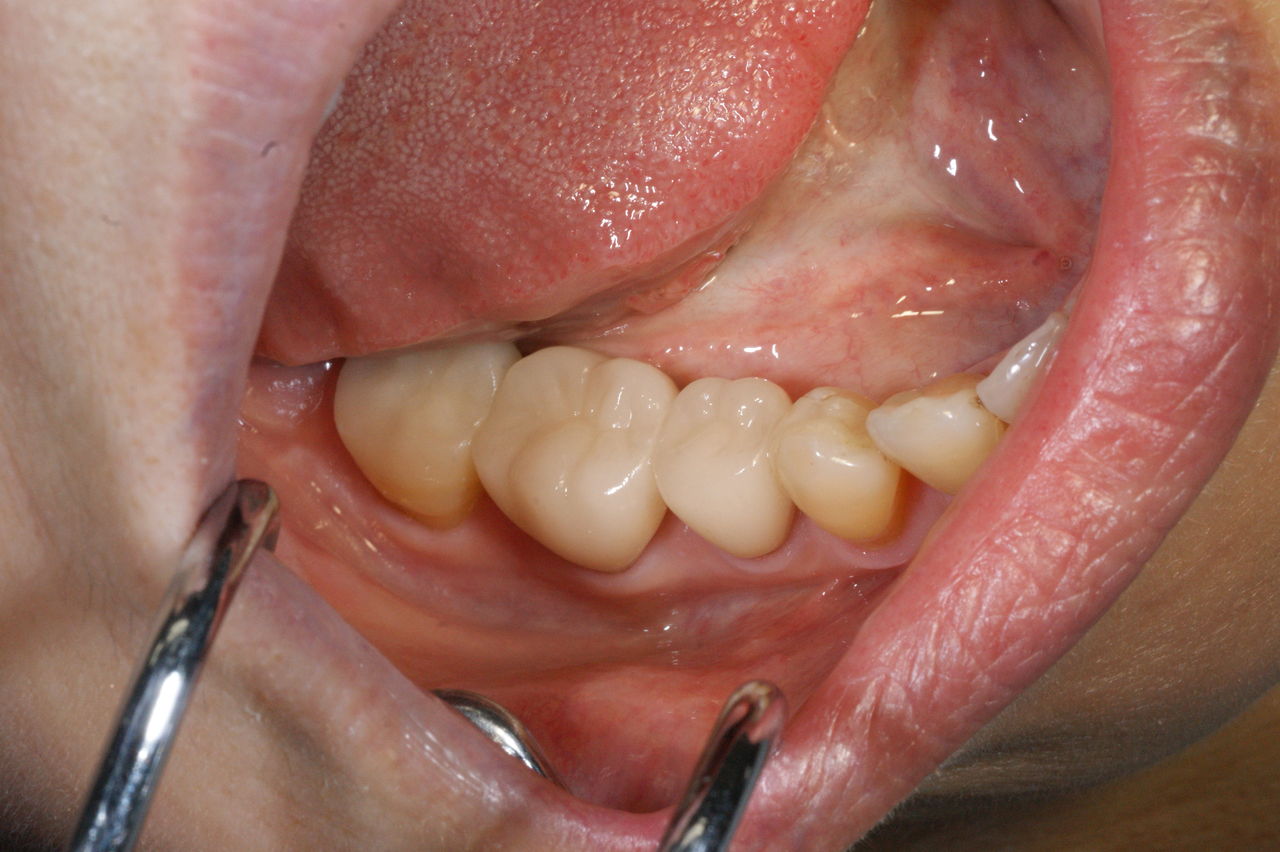

425.審美性 2019年06月21日 14:51 開口時、真っ先に金属歯が眼に入ります。 人工的な装着物が入っているのに、それを感じさせず、未治療の歯と調和して、自然に見えること。それが審美の審美たる所以ではないでしょうか!?(大) 「審美治療」カテゴリの最新記事 「修復治療」カテゴリの最新記事 < 前の記事次の記事 > コメント コメントフォーム 名前 コメント 評価する リセット リセット 顔 星 投稿する 情報を記憶